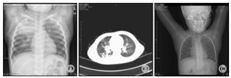

4例X线检查均示肺实质病变。例1,病程11 d CT示右上肺片状高密度影,病程20 d CT示双肺多个大小不等囊状影,右上肺显著。见图1A、图1B;3个月后复查胸片肺炎基本吸收,见图1C。例2,病程15 d肺CT:左侧胸廓略塌陷,左肺上叶大片状密实影,内见液平囊状影,见图2A、图2B;18个月后复查肺CT示左上肺脓肿消失,留有部分肺不张、条索影,见图2C。例3,病程6 d胸片示右上肺大片状高密度影,病程17 d肺CT示右上中肺大片及点状高密度影,右下肺背段多个厚壁空洞,呈簇状沿支气管分布,纵隔淋巴结大,见图3A、图3B。3个月后复查胸片肺炎基本吸收,见图3C。例4,病程5 d胸片示左上肺组织坏死,见图4A。0.5年后复查胸片提示炎症较前明显吸收,见图4B。

注:A:2010-02-08 CT示左上肺脓肿;B:2010-02-08 CT示左上肺脓肿(冠状位);C:2011-07-18 CT示左上肺部分肺不张、条索影,左下肺代偿性肺气肿